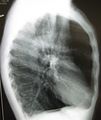

الپاثولوجيا العيانية للرئة تظهر انتفاخ الرئة المركزي بسبب التدخين. | |

فقاعة رئة كما تبدو عند تصوير الصدر بالأشعة السينية لدى شخص يعاني من داء الانسداد الرئوي المزمن الحاد